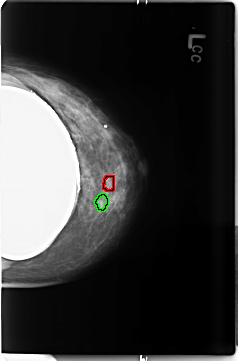

B_3497_1.LEFT_MLO

FILE: B_3497_1.LEFT_MLO.OVERLAY

TOTAL_ABNORMALITIES 2

ABNORMALITY 1

LESION_TYPE CALCIFICATION TYPE PUNCTATE-PLEOMORPHIC DISTRIBUTION CLUSTERED

ASSESSMENT 4

SUBTLETY 3

PATHOLOGY MALIGNANT

ABNORMALITY 2